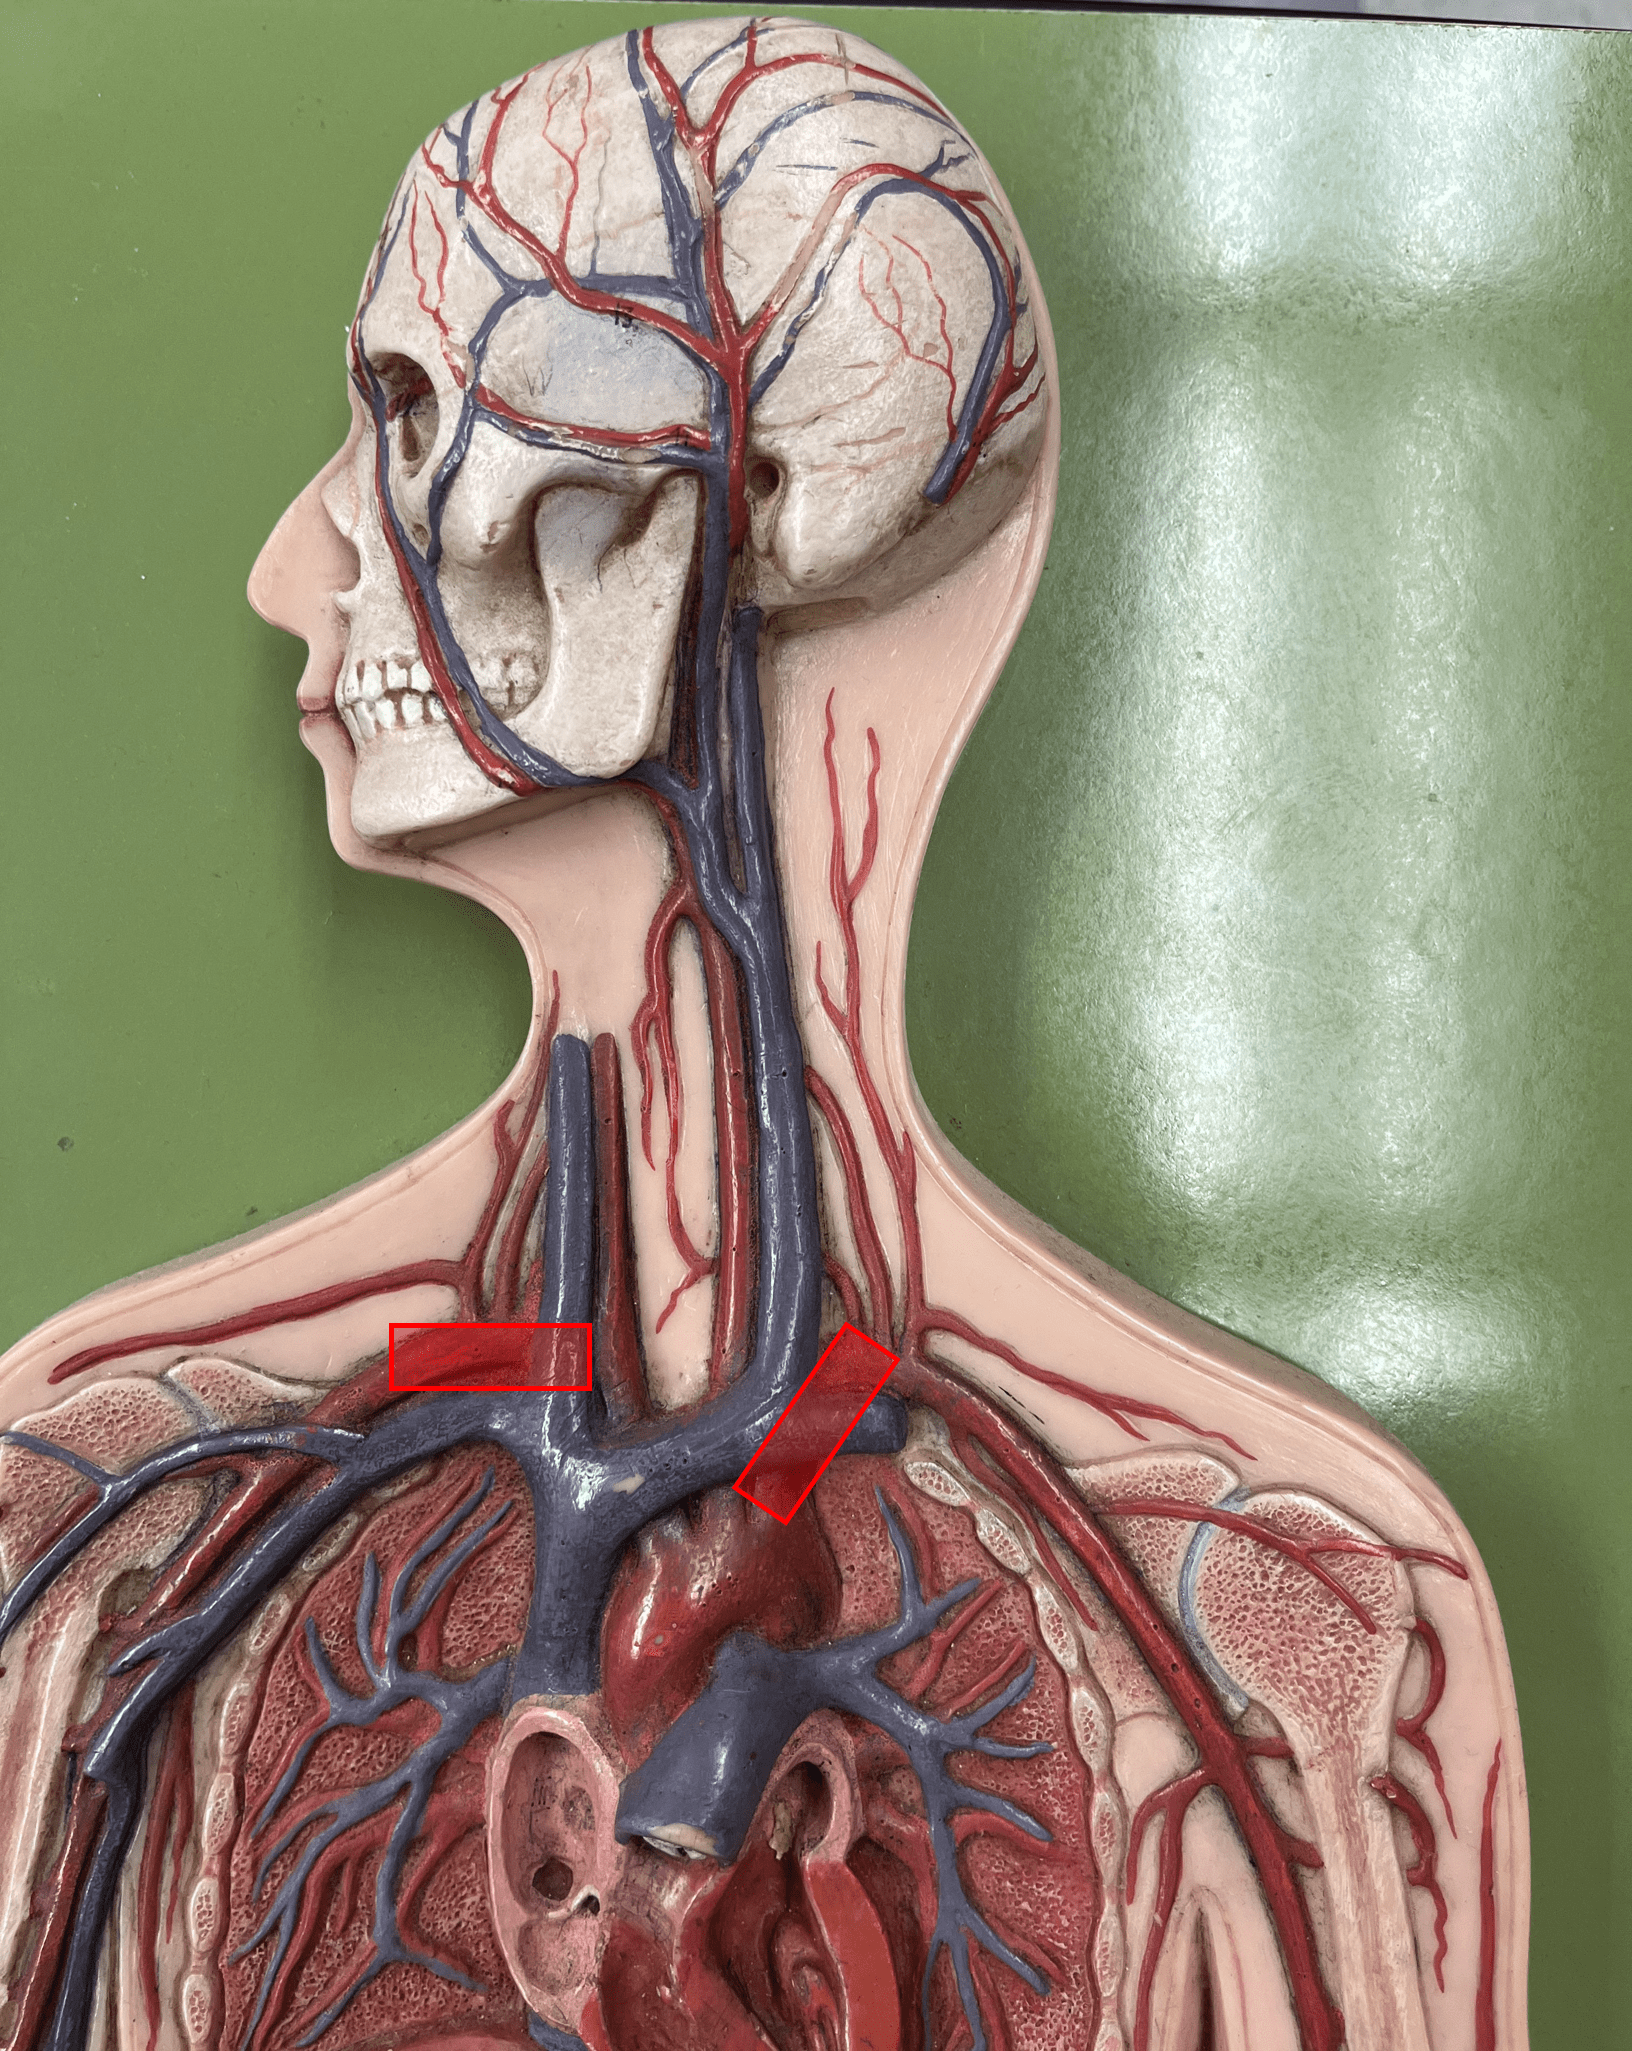

common carotid artery

• An artery of the head and neck.

• Originates from the brachiocephalic trunk (R.) or the aortic arch (L.).

• Supplies the head and neck through its branches.

• Originates from the brachiocephalic trunk (R.) or the aortic arch (L.).

• Supplies the head and neck through its branches.

internal carotid artery

• An artery of the head and neck.

• Originates from the common carotid artery.

• Supplies the cerebrum through its branches.

• Laterally, the middle artery of the neck.

• Originates from the common carotid artery.

• Supplies the cerebrum through its branches.

• Laterally, the middle artery of the neck.

vertebral artery

• An artery of the head and neck.

• Originates from the subclavian artery.

• Supplies the spinal cord, meninges, and neck muscles.

• Laterally, the posteriormost artery of the neck.

• Originates from the subclavian artery.

• Supplies the spinal cord, meninges, and neck muscles.

• Laterally, the posteriormost artery of the neck.

subclavian artery

• An artery of the thorax.

• Originates from the brachiocephalic trunk (R.) or the aortic arch (L.).

• Supplies its branches.

• Originates from the brachiocephalic trunk (R.) or the aortic arch (L.).

• Supplies its branches.

subclavian vein

• A vein of the thorax.

• Drains the axillary vein.

• Empties into the brachiocephalic vein.

• Drains the axillary vein.

• Empties into the brachiocephalic vein.